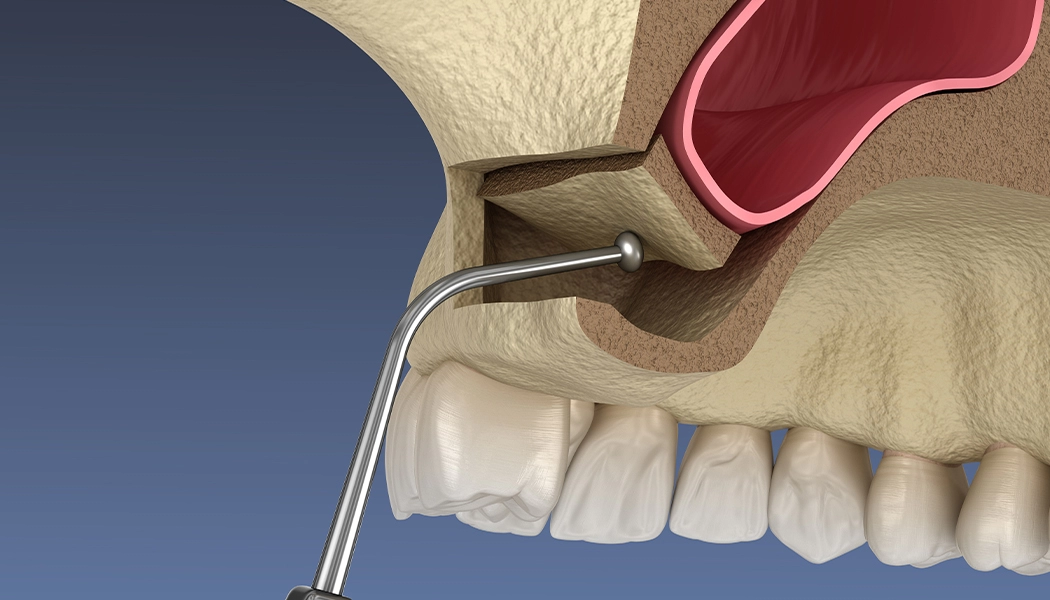

Показанием к проведению открытого синус-лифтинга является высота костной ткани менее 6 мм в области зубов, примыкающей к гайморовой пазухе. При открытом синус-лифтинге производится разрез слизистой, отслаивается слизисто-надкостничный лоскут, в передней стенке пазухи формируется перфорационное отверстие. Далее отслаивается слизистая самой пазухи, укладывается костный материал, после отверстие перекрывается специальной мембраной и слизисто-надкостничный лоскут ушивается.